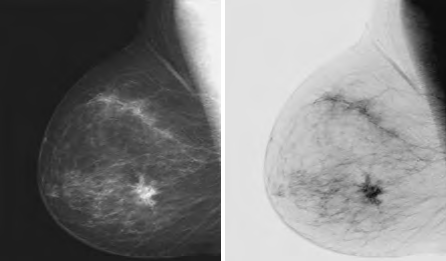

線性變換包括恒等變換和負變換。

這種變換適用于增強嵌入圖像暗區的白色或灰色細節。例如,在數字X線照片中分析身體結構組織。